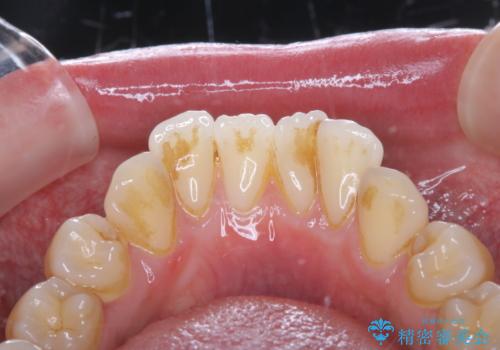

着色は少ない口腔内でしたが、染め出しをしてエアフローを行いました。

汚れが少なく見える口腔内でも染め出しをすると歯茎の近くなどに汚れが溜まっているのがわかります。

エアフローを行い、着色やバイオフィルム・歯垢(プラーク)が除去され歯の表面に艶が出ました。